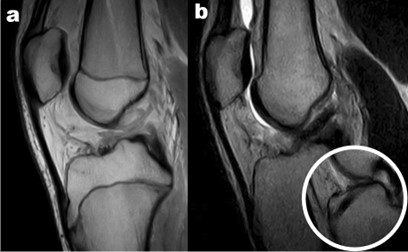

Figura 1: Lesione di LCA in paziente di 7 anni con immaturità scheletrica

Le lesioni del LCA in età pediatrica rappresentano meno del 5% di tutte le lesioni dell'LCA, ma la loro incidenza è aumentata di circa il 2-3% all’anno negli Stati Uniti, grazie sia a una maggiore esposizione sportiva dei giovani sia ai progressi nelle tecniche di imaging (Figura 1) [1]. In passato, molti specialisti rimandavano la ricostruzione del LCA fino al completo sviluppo scheletrico, temendo danni alle cartilagini di accrescimento. Tuttavia, il trattamento conservativo tende a causare instabilità articolare con elevata incidenza di lesioni meniscali secondarie (fino al 70% dei casi) che predispongono a precoce artrosi [2]. D’altra parte, la ricostruzione eseguita troppo precocemente, se non condotta con attenzione, può provocare arresto di crescita o deformità assiali. Nonostante le linee guida emesse da organismi internazionali, manca un consenso univoco riguardo a indicazioni, tempistiche e tecniche chirurgiche [3]. Al fine di colmare questa lacuna, proponiamo un modello gestionale che unisce le migliori evidenze disponibili all’esperienza clinica, indirizzando le decisioni terapeutiche negli atleti giovani con cartilagini aperte.